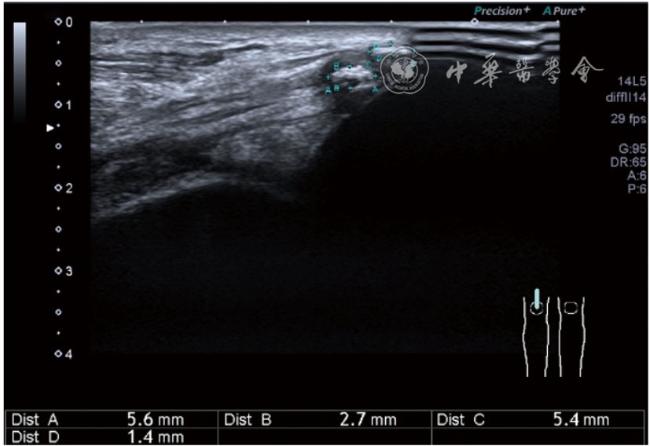

2.膝关节静态结构治疗。动力平衡失调后,继发静态结构变化,出现内外侧副韧带、交叉韧带、脂肪垫、半月板等结构变化。这里介绍半月板与交叉韧带的处理。(1)膝关节静态结构半月板治疗。在膝关节骨关节炎中主要是突出和损伤。突出主要发生于膝内翻引起的内侧半月板突出,引起内侧副韧带的张力增高。内侧半月板与内侧副韧带相连,是引起膝关节内侧疼痛的主要原因之一。治疗主要是针刀剥离松解,部分损伤可行PRP注射。①半月板突出针刀剥离松解治疗。针刀治疗主要是松解和减压,缓解疼痛,不能复位。以内侧半月板突出治疗为例。患者平卧位,髋轻度外展外旋,膝关节屈曲30°,膝下垫一软枕。选用10 MHz超声探头,穿刺区域常规消毒,探头涂抹耦合剂后套入无菌手套碘伏消毒或使用无菌耦合剂。将探头置于患者皮肤表面,内侧关节间隙长轴扫查,找到半月板突出最高点,用25G针头,抽吸1%利多卡因3 ml逐层麻醉直到半月板。选用直径1 mm的Ⅰ型2号针刀从头侧向足侧方向在内侧副韧带与半月板之间,以及半月板内部进行剥离松解3~5刀拔出针刀(图13),局部压迫5分钟,无菌敷料覆盖。②半月板损伤PRP注射治疗。半月板损伤主要表现为髌下痛,伸膝加重,查体在髌下髌韧带与侧副韧带之间,沿关节间隙有固定或局限性压痛,伸膝过程中尤为明显。MRI可示半月板断裂、损伤。如果出现绞索,严重影响功能需手术治疗。半月板损伤治疗,以注射PRP修复为主。以内侧半月板后角损伤为例。患者俯卧位,治疗前准备同半月板突出针刀剥离松解治疗。选用25G注射针头,抽取1%利多卡因2 ml局部麻醉后,制取1.5 ml PRP,穿刺到达半月板撕裂处注射,注射完毕后出针(图14),局部压迫2分钟,无菌敷料覆盖。(2)膝关节静态结构交叉韧带治疗。膝关节骨关节炎交叉韧带损伤多为部分损伤,治疗早期主要为药物或PRP注射,效果不佳时针刀做止点松解。①后交叉韧带损伤药物注射治疗。主要治疗韧带肿胀、无明显断裂患者。患者俯卧位,膝关节伸直位。一般选用10 MHz超声探头,治疗前准备同半月板突出针刀剥离松解治疗。将探头置于患者皮肤表面,后交叉韧带长轴扫查,找到胫骨止点,选用22G长针头,抽吸1%利多卡因3 ml+曲安奈德10 mg,从头侧向足侧方向穿刺到后交叉韧带胫骨止点部位的韧带表面进行注射,注射结束拔出针头(图15),局部压迫2分钟,无菌敷料覆盖。②前交叉韧带损伤PRP注射治疗。患者仰卧位,膝关节伸直。选用10 MHz超声探头,治疗前准备同半月板突出针刀剥离松解治疗。将探头置于患者皮肤表面,短轴扫查,找到前交叉韧带胫骨止点,选用25G针头,抽吸1%利多卡因3 ml逐层麻醉直到韧带止点部位,制备PRP 3 ml注射到前交叉韧带显露部位,注射结束拔出针头(图16),局部压迫2分钟,无菌敷料覆盖。③前交叉韧带损伤针刀剥离松解治疗。体位与治疗前准备同前交叉韧带损伤PRP注射治疗。短轴扫查找到前交叉韧带胫骨止点,选用25G针头,抽吸1%利多卡因3 ml逐层麻醉直到韧带止点部位,选用直径0.6 mm的Ⅰ型2号针刀从外侧向内侧于前交叉韧带胫骨止点部位剥离松解3~5刀拔出针刀(图17),局部压迫5分钟,无菌敷料覆盖。

图17 超声引导下前交叉韧带损伤针刀剥离松解治疗